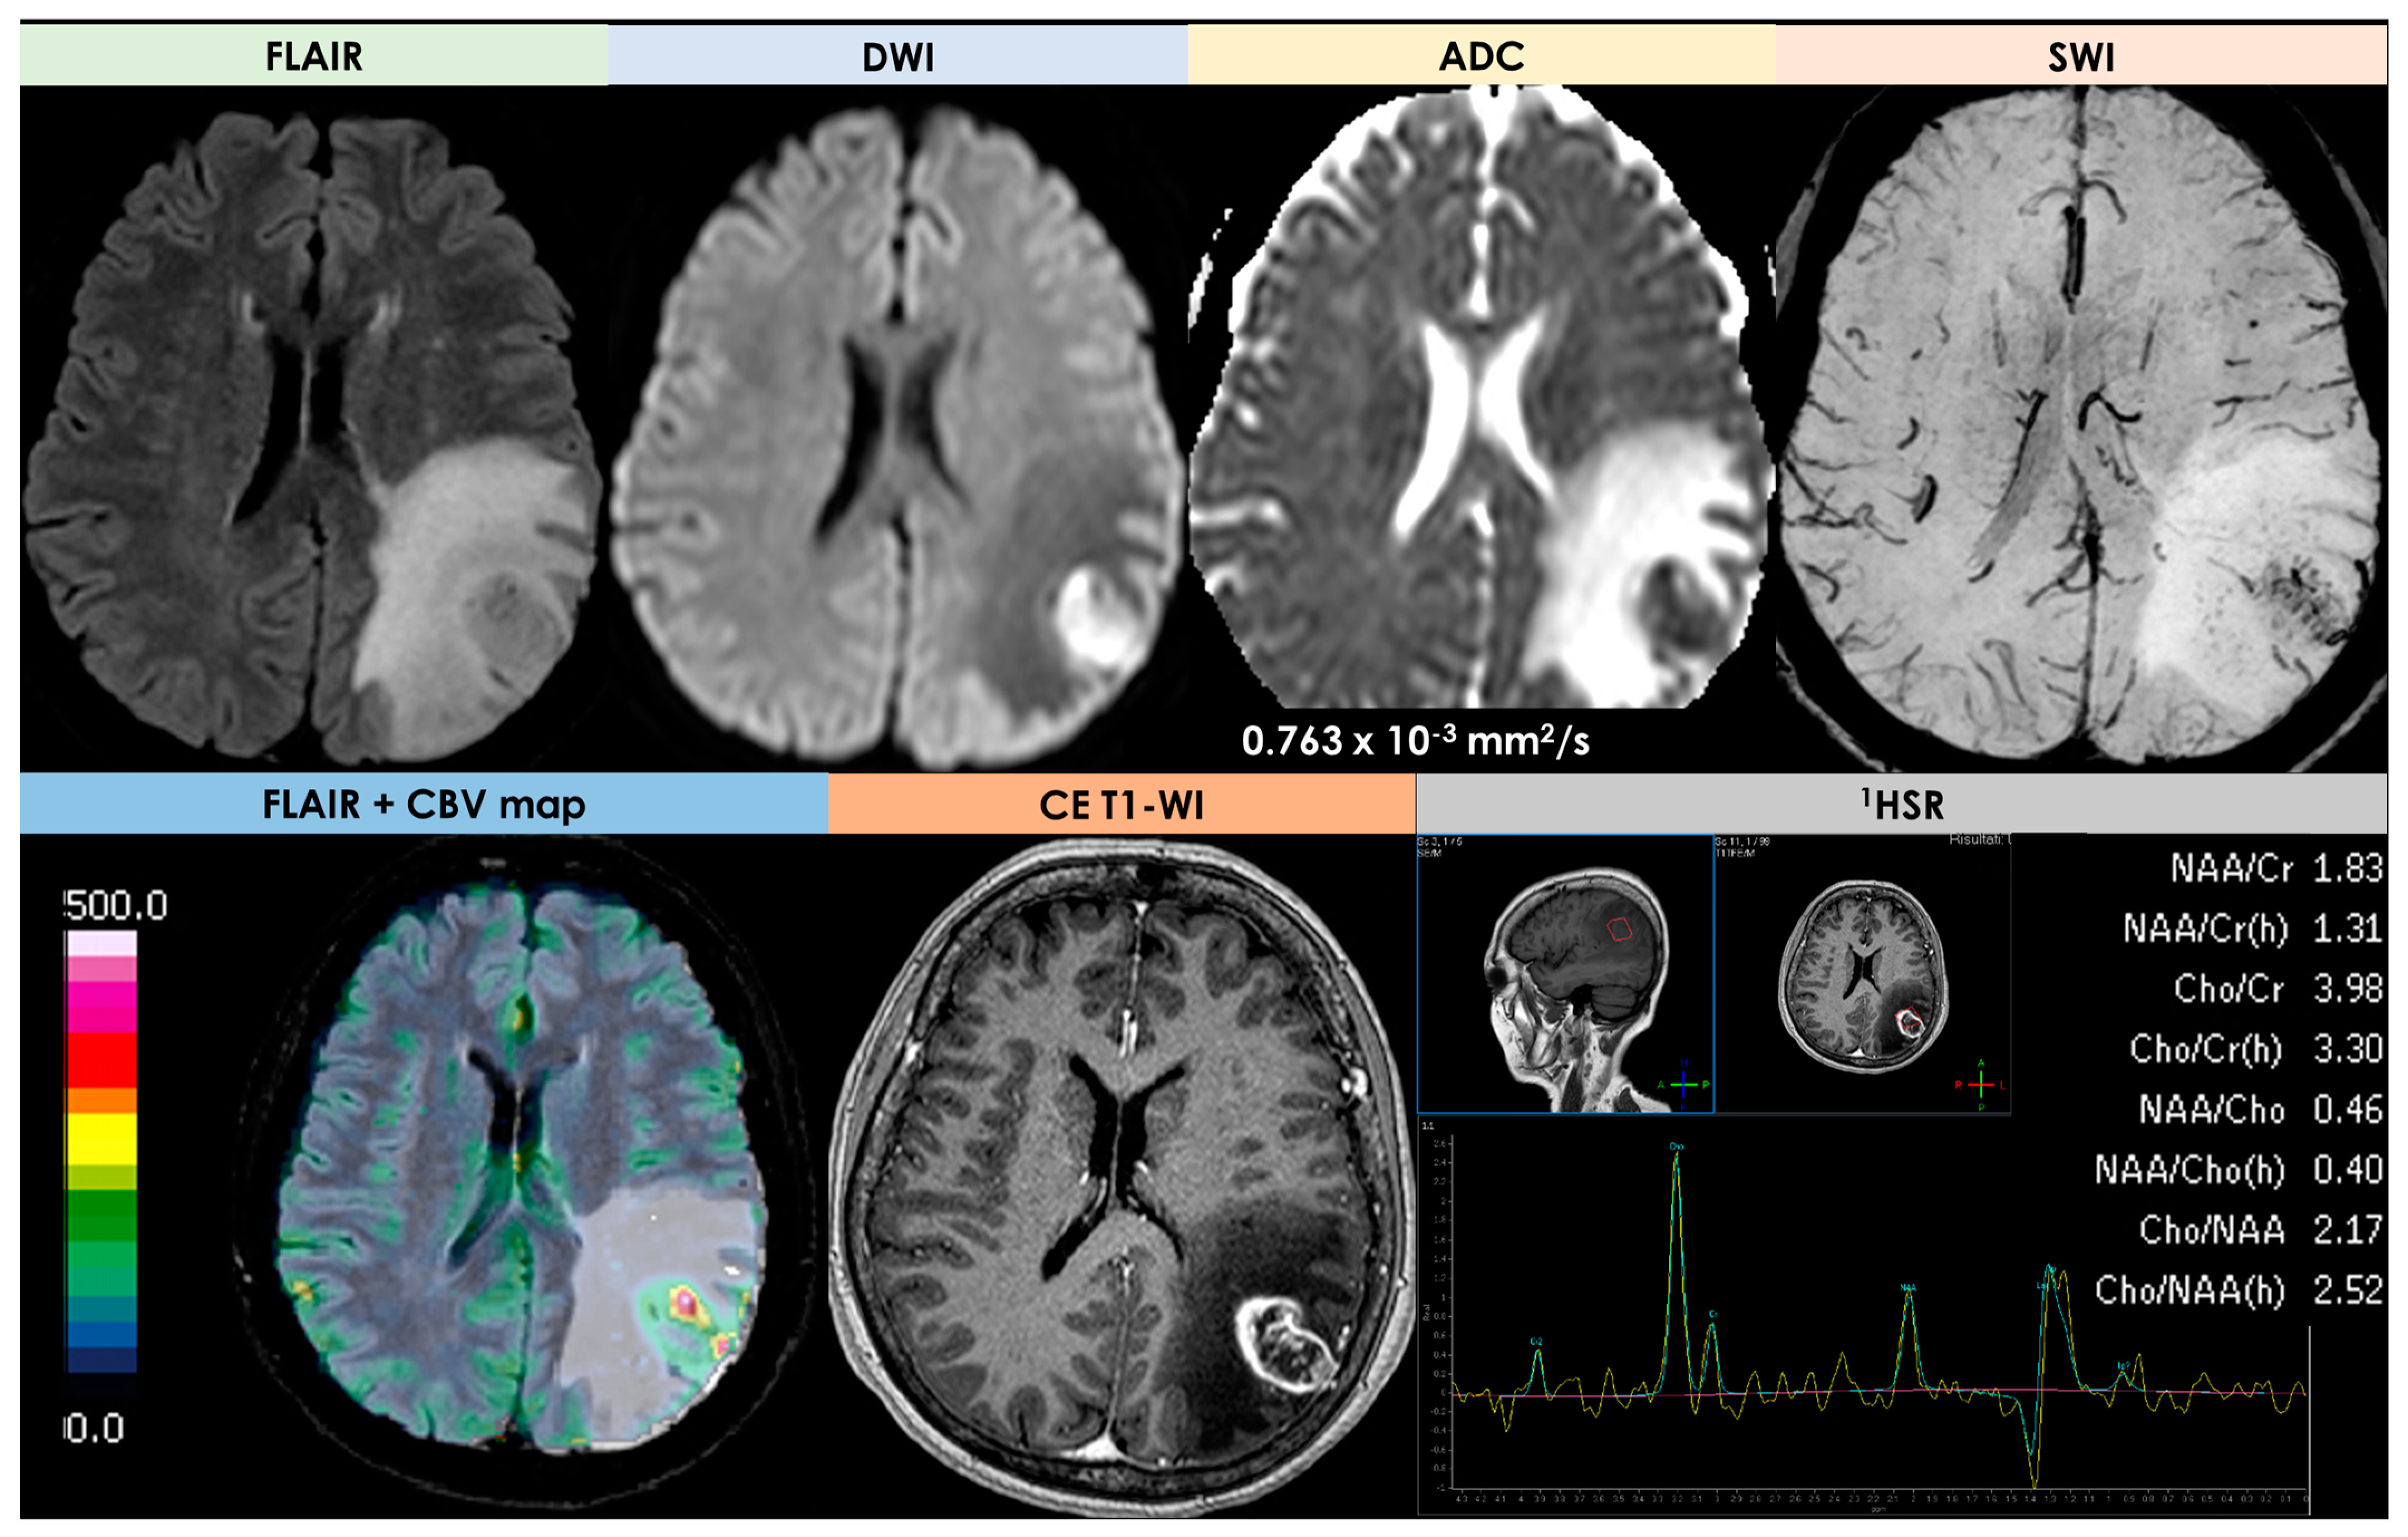

3.4. High-Grade Gliomas

| DWI/ADC | Hyperintense on DWI/hypointense on ADC maps Decreased FA values in lesions | High ADC values in center of lesion and relatively low ADC values in periphery of lesion Threshold for the minimum ADC value for distinguishing TDLs from PCNSL is 0.556 × 10−3 mm2/s | Hypointense in DWI and ADC | Hypointense on DWI and ADC | “Eccentric target sign” consisting of an eccentric nodule along the rim of an enhancing lesion on T1-WI ADC > 1.6 × 10−3 mm2/s suggestive of toxoplasmosis |

| DSC-MRI | rCBV lower than HGG Characteristic TIC | Few data with variable findings | rCBV usually higher than PCNSL, but variable findings | No data | rCBV lower than that in necrotic glioblastomas and metastases |

| Spectroscopy | Elevated lipid peaks and high Cho/Cr ratios | Increased Cho- peak Decreased NAA peak Increased Cho/NAA ratio | Elevated lipid peaks High Cho/Cr ratio | No data | No data |